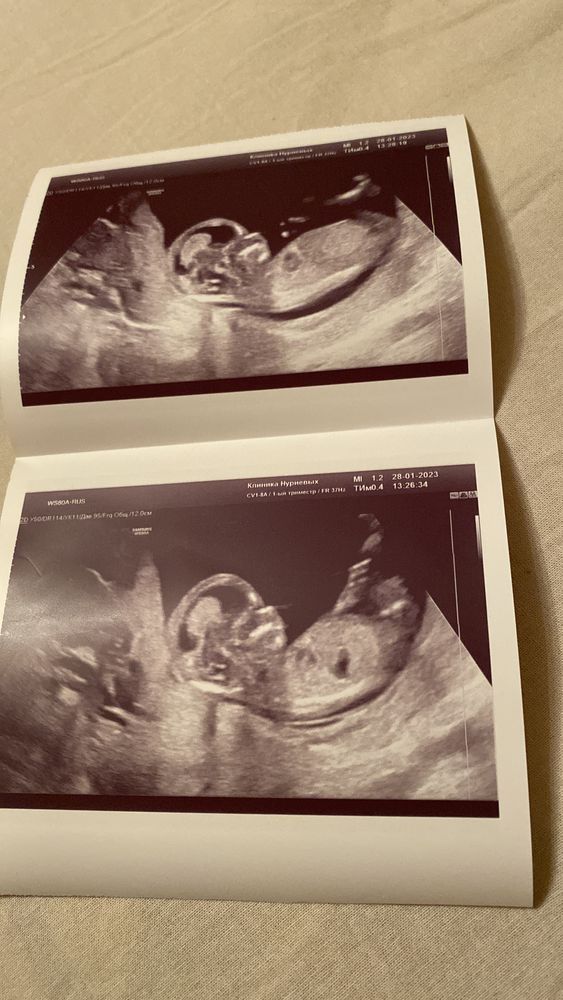

на 13 недели делали первый скрининг.

на узи в 13 недель предположили, что похож на мальчика, может кто то разбирается в этом, почему то в глубине души кажется, что девочка.

На таком сроке по УЗИ пол точно не определить. Можно только с 15 недель. Если сильно интересно- сдайте анализ крови, около 9 тысяч вроде стоит